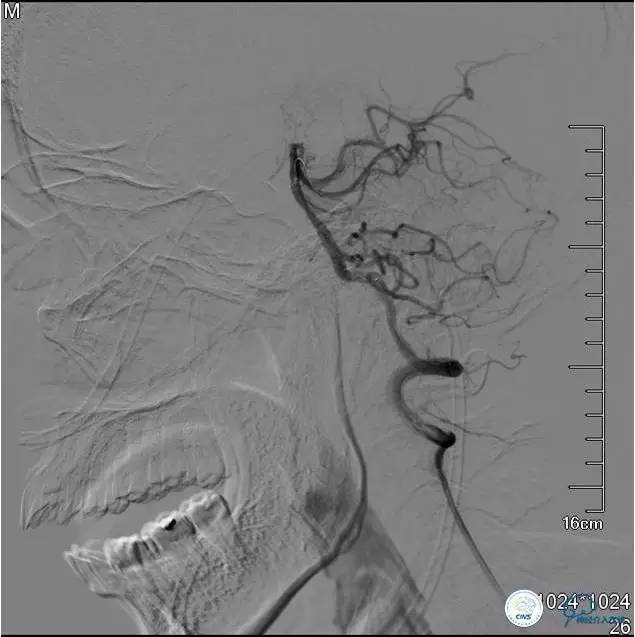

▼DSA:BA重度狭窄、右侧PCA开放。

DSA示TICI分级达到2b级(造影剂完全充盈,包括丘脑的供血,但排空延迟)。